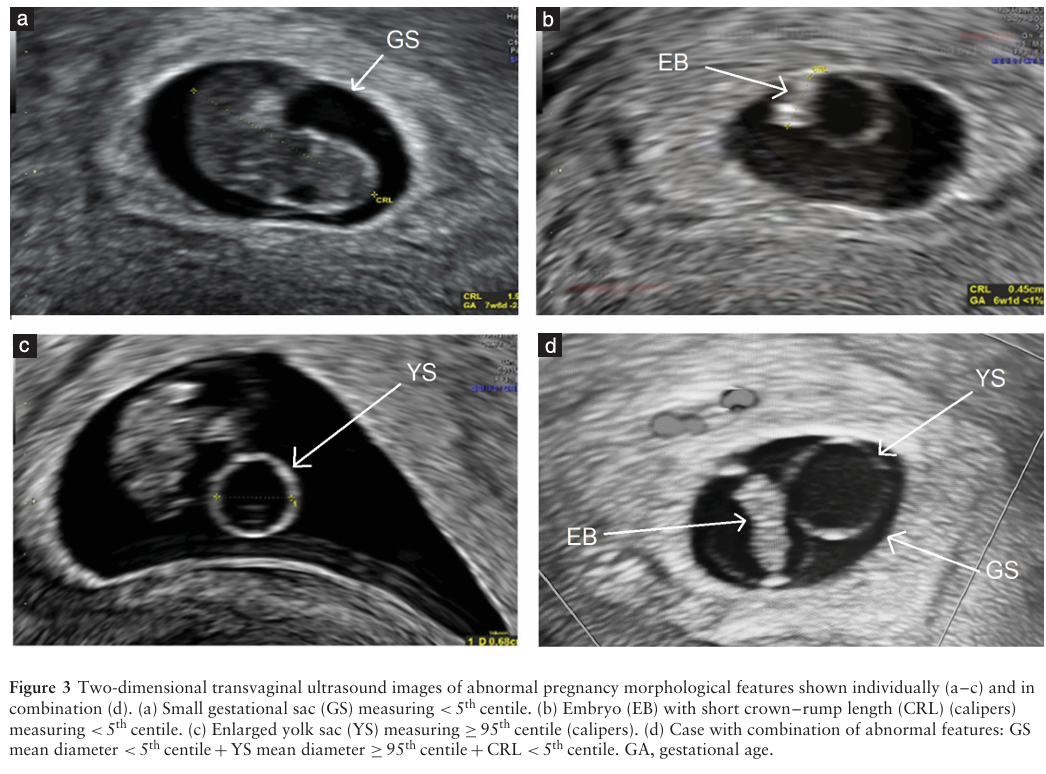

根据预设的超声形态学异常(单独和组合)的存在评估了异常核型的优势比(表3)。单独评估时,每个异常超声特征在所有孕周均与异常核型显著相关,其中CRL<第5百分位数显示出最高的OR(5.51(95%CI,2.53-12.01)P<0.001)。组合而言,非整倍体四联征(GSMD<第5百分位数+YSMD≥第95百分位数+CRL<第5百分位数+心动过缓)与异常核型显著相关,特别是在≤10周检查的病例中(OR,7.51(95%CI,2.41-140.22);P<0.001)。TVS上异常形态学发现的超声图像见图3。